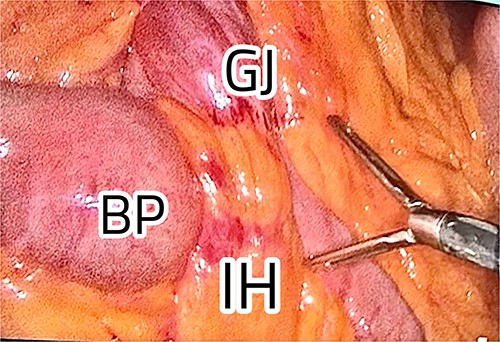

The patient was positioned with split legs. Five laparoscopic ports were used, and insufflation was obtained. Internal herniation was found at the site of the gastro-jejunal anastomosis, showing an apparent mesenteric twist due to adhesions found at Petersen’s space (Fig. 2). Adhesiolysis was carried out by extending the space, allowing the bowel limbs to un-twist, and placing them in the appropriate direction. The Petersen’s space was closed, and both limbs were fixed to adjacent structures to prevent future herniation. A methylene blue test was performed to check the integrity of the anastomosis. All the bowel loops were examined for adhesions and proper configuration (Fig. 3).

Restoration of the anatomy, fixation, and closure of Petersen’s space.